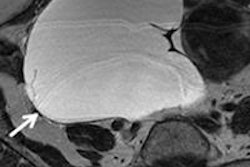

Stimulated Raman scattering (SRS) microscopy images. Left: brain metastasis from a lung carcinoma; center: human glioblastoma cells; right: infiltrative low grade oligodendroglioma, with tumor cells and an associated "chicken wire" blood vessel seen in blue. Credit: Orringer and Xie Labs.Aiming for the release of a commercial device within the next 18-24 months, the technology is being developed by a multipartner collaboration. Partners include Harvard University, where SRS microscopy was developed by the Xie group, and start-up company Invenio Imaging. The approach stimulates Raman scattering using two lasers whose difference in frequency is tuned to match the vibrational modes of lipids and proteins. The resulting images display lipids in green and proteins in blue, enabling protein-rich tumor cells to be detected.

The researchers used SRS microscopy to image samples from 19 patients with glioblastoma and three with epilepsy. As expected, there were marked qualitative differences between the two groups and between different types of tumor and normal brain tissue. Overall, tumor-infiltrated tissue exhibited higher cellularity, a protein-rich composition, and a lower density of axons. In a blinded online survey of three neuropathologists, the researchers demonstrated the utility of the images in detecting and identifying the degree of tumor infiltration matched that of H&E staining. They obtained very good agreement between the two techniques in a sample of seven patients.